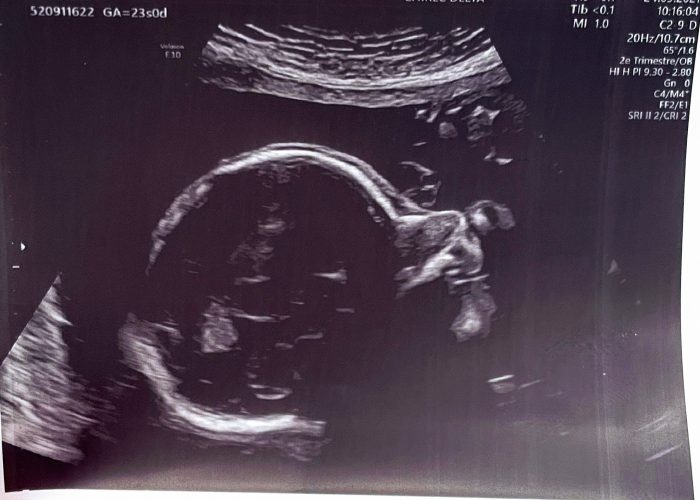

My (Second) Pregnancy Diary: Second Trimester Combination of Energy and Anxiety

Making of | November 16, 2021